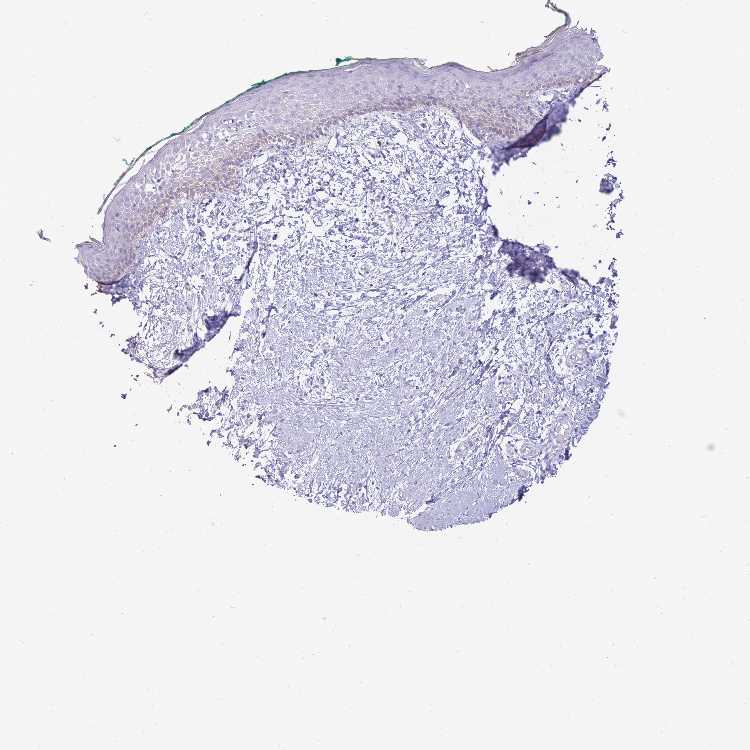

SKIN 1 - Antibody stainingi

Antibody staining in the annotated cell types in the current human tissue is reported as not detected, low, medium, or high, based on conventional immunohistochemistry profiling in selected tissues. This score is based on the combination of the staining intensity and fraction of stained cells.

Each image is clickable and will lead to virtual microscopy that enables deeper exploration of all samples and also displays staining intensity scores, fraction scores and subcellular localization as well as patient and tissue information for each sample.

Antibody HPA049112

Langerhans Not detected

Fibroblasts Not detected

Keratinocytes Not detected

Melanocytes Not detected